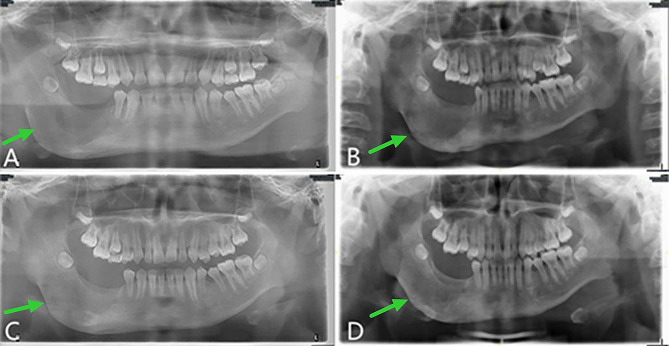

Fig. 4.

Follow-up panoramic oral radiogram after the second operation, displaying the continuous bone remodeling. A, 3 months postoperative. B, 4 months postoperative. C, 6 months postoperative. D, 10 months postoperative